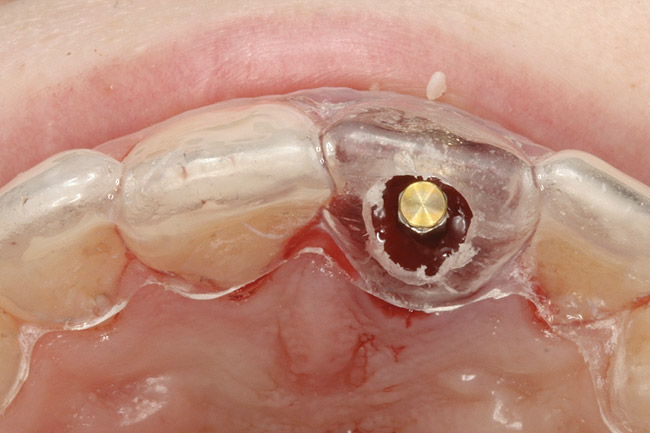

The osteotomy was started slightly palatally in alignment with the surgical guide, using a 2.1-mm precision drill (Figure 13) and finalized with shaping drills under copious external irrigation with sterile water. Special attention was paid to overcorrecting the osteotomy preparation toward the palate, where the bone is denser. An implant in this area—especially a tapered implant, as was used here—will usually veer toward the facial surface during insertion. Using the surgical guide to superimpose the central axis of the implant on the previous location of the central incisor’s cingulum facilitates accurate positioning (Figure 14).

Figure 13  Initial osteotomy preparation with 2.1-mm precision drill, site No. 9. Priority level: 3.

Figure 13

Figure 14  Appropriate alignment of immediate temporary abutment, central axis of implant with cingulum area of surgical guide, incisal view.

Figure 14